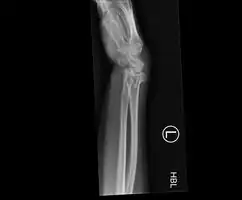

Colles fracture

The term Colles fracture is classically used to describe a fracture at the distal end of the radius, at its cortico-cancellous junction. However, the term now tends to be used loosely to describe any fracture of the distal radius, with or without involvement of the ulna, that has dorsal displacement of the fracture fragments. Colles himself described it as a fracture that “takes place at about an inch and a half (38mm) above the carpal extremity of the radius” and “the carpus and the base of metacarpus appears to be thrown backward”.[10] The fracture is sometimes referred to as a "dinner fork" or "bayonet" deformity due to the shape of the resultant forearm.